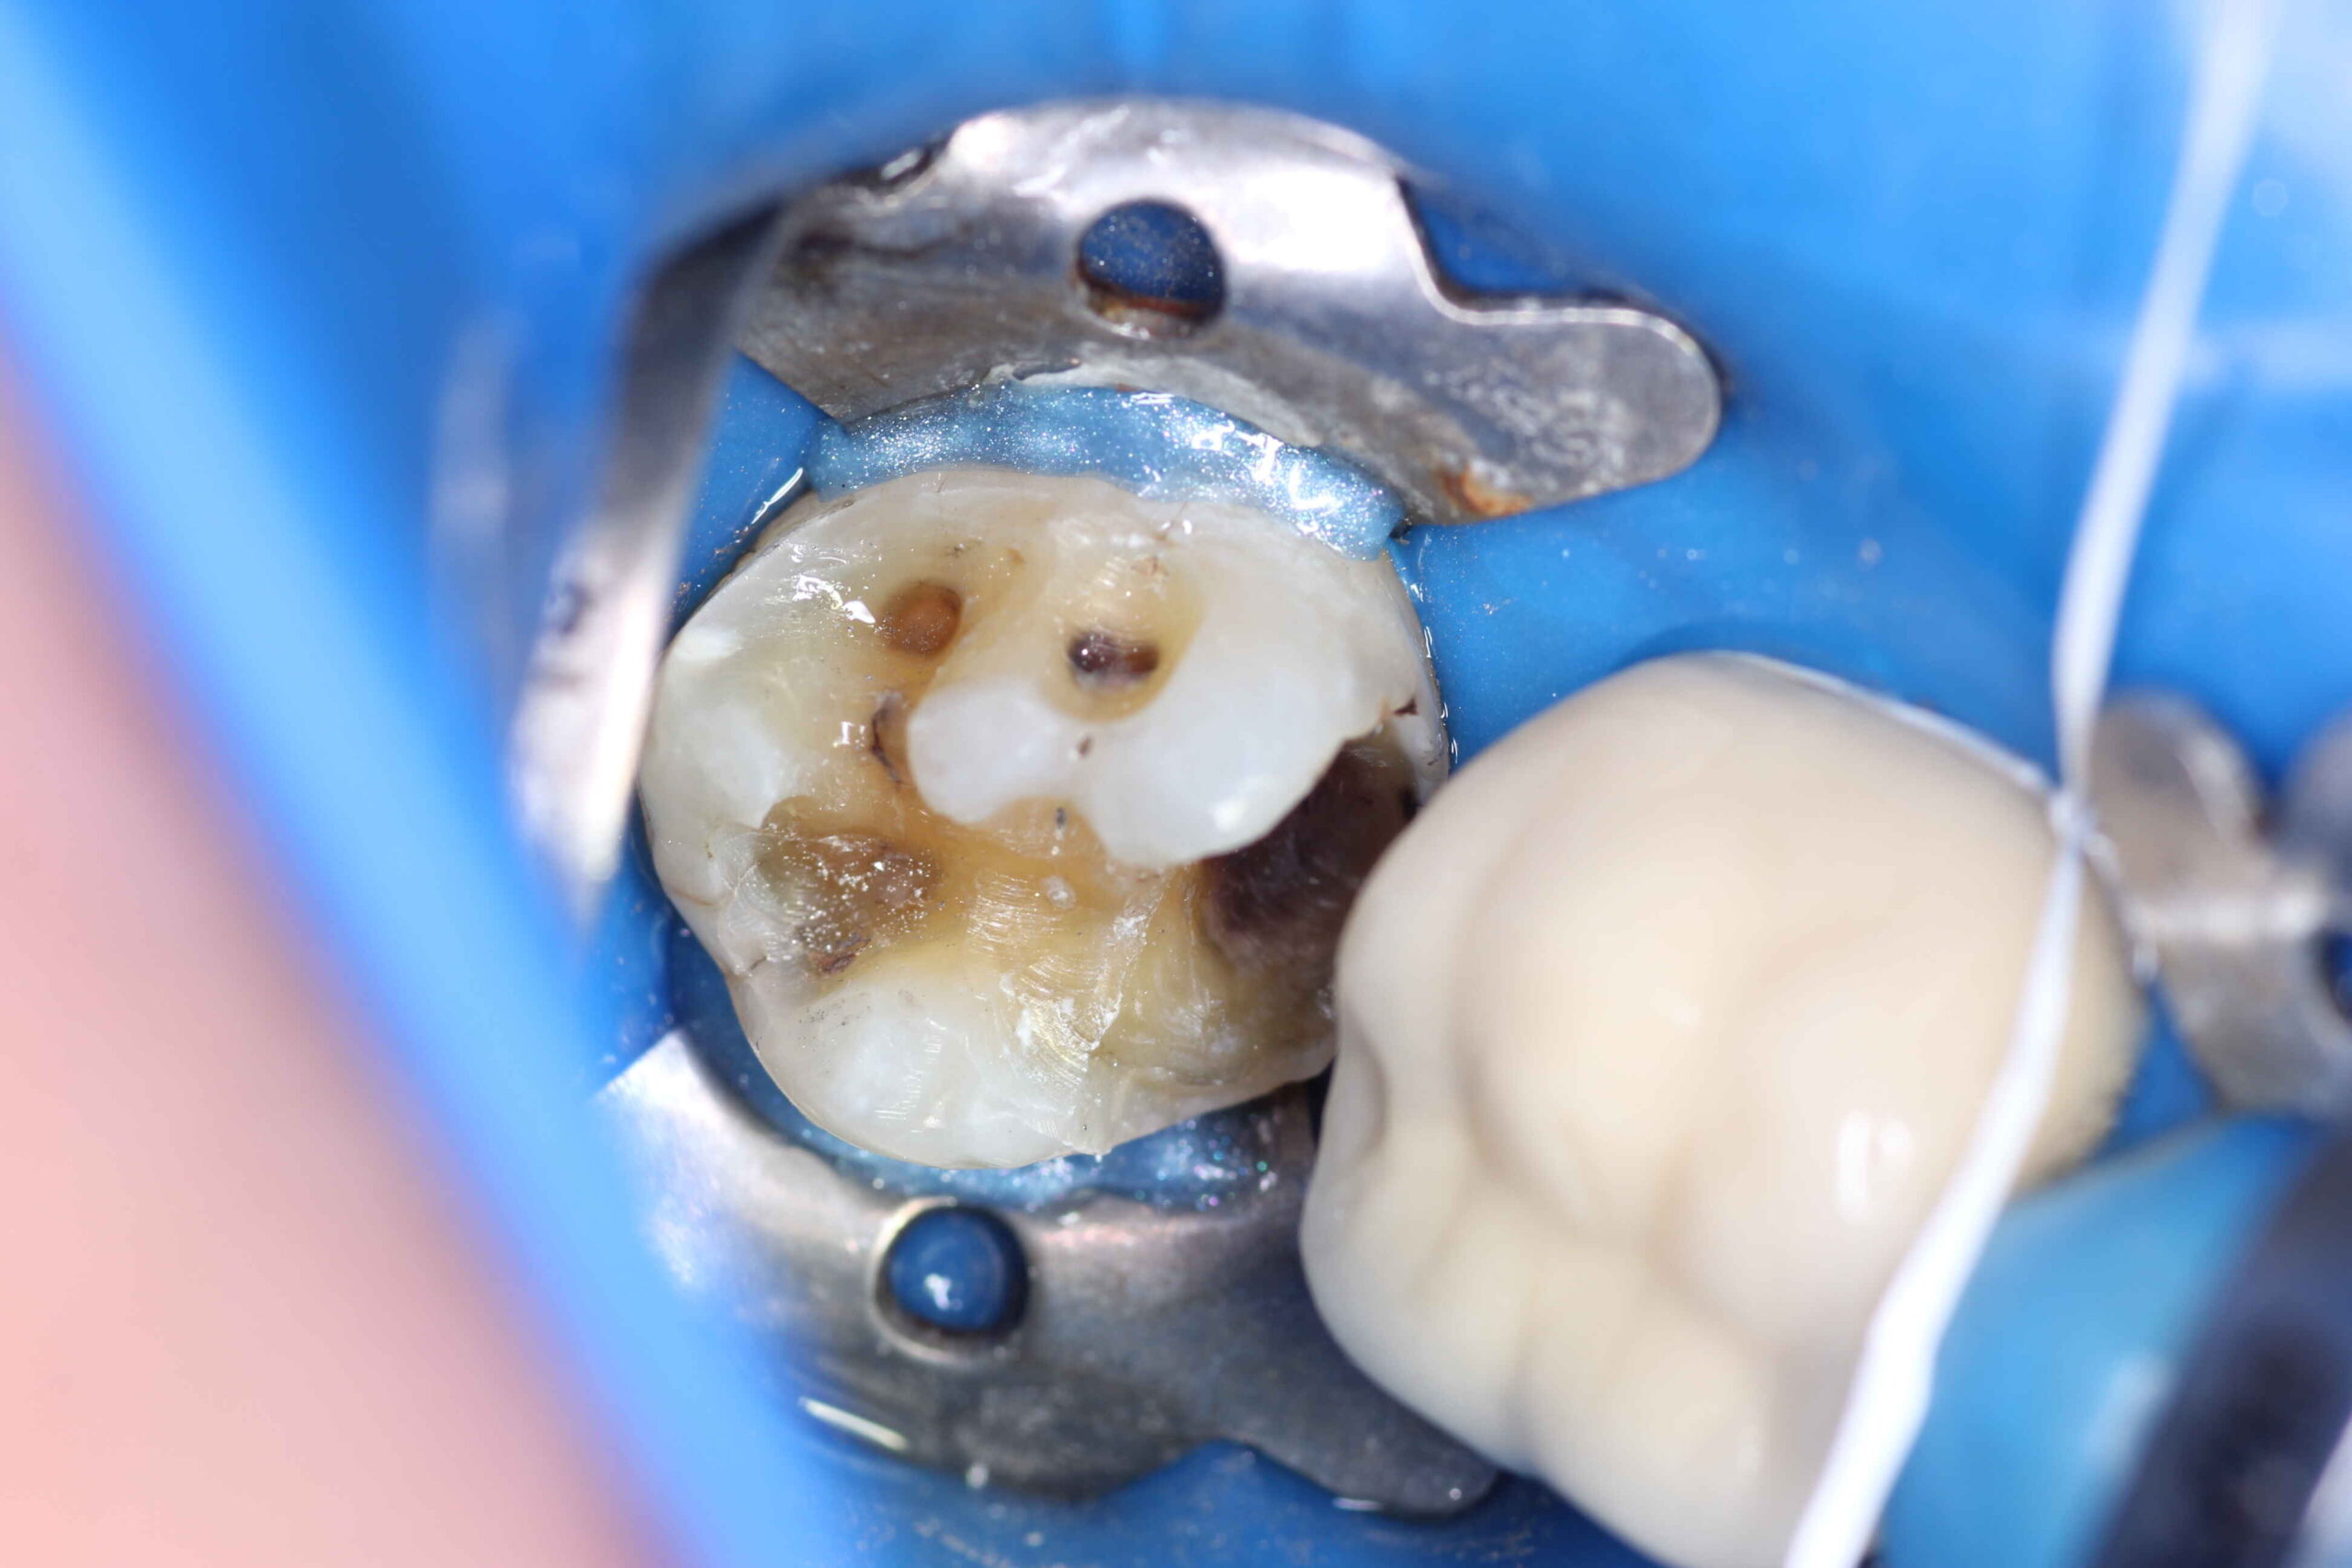

Você ainda tem restaurações metálicas (amálgama)?

Com o tempo, esse tipo de material pode causar tensão na estrutura do dente, aumentando o risco de fraturas dentais.

A substituição por resina composta é uma ótima alternativa, pois:

Se você possui restaurações antigas de amálgama, vale a pena realizar uma avaliação odontológica para verificar a necessidade de troca.